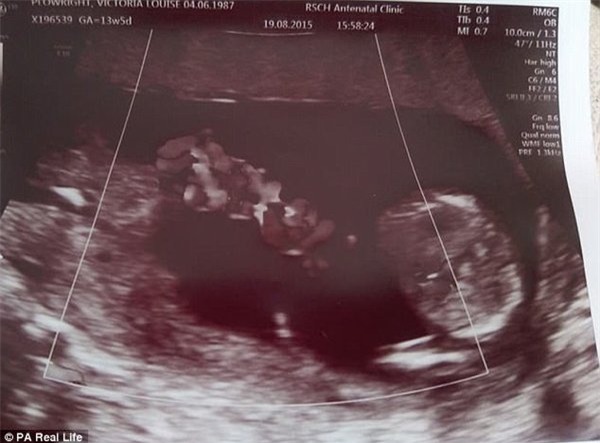

Vào buổi siêu âm ở tuần thứ 10, Vicky đã được bác sĩ thông báo rằng hai em bé song sinh trong bụng cô có chung túi ối, vì thế, có nguy cơ tử vong rất cao, lên đến 50%

Thế nhưng, một điều kì diệu đã xảy ra khi Vicky đi siêu âm vào tuần thứ 12 của thai kỳ. Trên màn hình siêu âm, hai bé trai trong bụng cô đã di chuyển đến một tư thế an toàn cho cả hai, khiến sợi dây rốn khó có thể rối vào nhau được, đó là tư thế ôm lấy nhau. Đồng thời, tư thế này cũng giúp hai bé có được nhiều không gian phát triển nhất có thể.

Hình ảnh diệu kỳ khi hai bé Reuben và Theo ôm lấy nhau trong bụng mẹ, nhờ đó, cùng nhau thoát khỏi lưỡi hái tử thần